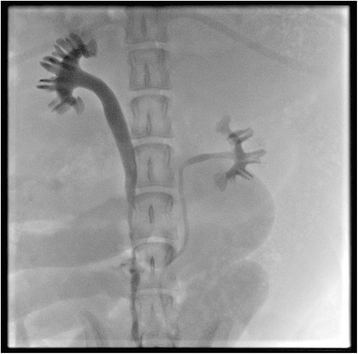

摘要:输尿管缺损和重建泌尿狭窄仍然是个问题。我们旨在研究锥形非血管化膀胱移植物作为一种新的输尿管重建替代物的可能性。方法:本实验进行了九条比格犬研究。在全身麻醉下,用5–6 cm长全层移植游离于膀胱前壁上,锥形1/3至1/2厚,保留尿路上皮表面。5 厘米右侧输尿管中段切除后锥形膀胱沿长轴移植然后分别吻合输尿管的上部和下部。输尿管重建术后8周后通过膀胱逆行尿路造影。动物安乐死后,对新尿管进行病理学检查。结果:术后随访无严重并发症发生。尿路造影显示有尿排出,无瘘管或狭窄。该新尿管病理检查显示尿路上皮管腔。健康黏膜下层、肌层及周围结缔组织均有滋养血管。结论:我们的研究提示,在动物模型中,锥形的非血管化膀胱移植物的输尿管重建是可能的。预计进一步的研究将证实长期和功能结果。关键词:动物模型 膀胱移植 非血管化 输尿管重建背景:输尿管损伤通常源于外伤或医源性原因。在大多数情况下,无附加材料的端端吻合术可以应用于短段输尿管缺损或狭窄的治疗。此外,一些经典的手术修复方法已得到公认,包括使用膀胱肌瓣输尿管成形术,回肠输尿管置换、肾自体移植。但这些传统方法在实际应用中存在一定的局限性。回肠代肠由于肠黏膜的特点,术后有多种并发症,包括重吸收的铵和粘液分泌,随后可能引起尿路感染及结石形成。肾移植是一个复杂的过程与可能的感染和肾功能丧失有关。关于重建材料,膀胱尿道瓣(或移植物)膀胱腔衬里,类似于输尿管,似乎是理想的输尿管置换术。我们假设使用非血管化膀胱移植物重建输尿管上段或中段是可能的。主要的问题是膀胱移植物能否在没有血管蒂的情况下存活。本研究的主要目的是研究一种新的方法,即利用锥形非血管化膀胱移植物重建犬模型的输尿管。方法:比格犬的平均体重为10.6公斤(8.4 –12.2 公斤)。犬被单独安置在受控环境中的不锈钢笼子里。自由采食和饮用纯水。选择右侧输尿管作实验手术,左侧为对照组。聚维酮碘进行皮肤消毒。然后,头孢唑啉肌注。该手术是在普通气管插管麻醉下进行的。麻醉是通过静脉注射异丙酚(4 毫克/公斤),利多卡因(1 毫克/公斤),地西泮(0.3 毫克/公斤)和维持麻醉是异氟醚与100%的氧气。剖腹手术采用经腹正中切口。检查腹腔脏器以排除任何可能的异常,尤其是泌尿系统。一个矩形区域由四个松结扎在每个顶点上的充盈的膀胱前壁上标记,其体积约为30-40 毫升。区域设计了长5–6厘米宽1厘米 。全层切除后,膀胱移植物暂时保存在生理盐水中,轻轻挤压直至变苍白。通过膀胱造瘘,一4.7-fr输尿管支架逆行插入右输尿管管口。右输尿管从腹膜后组织分离出。然后从中间剪掉大约5 厘米。用眼科剪将非血管化膀胱片剪成锥形1 / 3到1 / 2的厚度(2–3 毫米),保持尿路上皮表面完整。此后,沿长轴进行锥形膀胱移植内置支架。移植管的两端分别与输尿管的上部和下部的残余部分缝了四针。检查吻合口出血及漏尿情况,3~4针闭合腹部筋膜。手术伤口逐层闭合。所有的动物术后3天都接受了头孢唑啉钠和氟比洛芬。头孢唑啉钠又继续服用一天。每天监测两次特定体征,包括体温、呼吸频率、脉搏、食欲、活动、排便和排尿。手术伤口在监测时进行观察和消毒。在手术后的几个小时液体饮食,第二天就开始了常规饮食。输尿管支架维持到术后6周, 通过一个简单的膀胱造瘘去除。重建术后8 周,由A 5-FR管逆行尿路造影.通过另一个膀胱造瘘术评估泄漏或狭窄的可能性。在全身麻醉下静脉注射氯化钾对动物进行安乐死。摘取右肾、输尿管(连同周围结缔组织)和切除部分膀胱,立即进行福尔马林固定。标本石蜡包埋,苏木精-伊红染色。两位有经验的泌尿生殖病理学家分别完成了显微镜检查。结果:实验结束时,9条犬都接受了手术并存活了下来。都进行有规律的饮食和活动。一例犬腹部切口出现皮下脓肿,经手术清创治愈。无明显并发症,包括严重肉眼血尿、腹腔感染或漏尿。7只动物的输尿管支架放置到位,直至取出,其余两只均已从泌尿系统取出。排尿节律无明显变化。经安乐死后探查,腹腔内无血肿、感染或漏尿。右侧输尿管重建段纤维粘连,在右肾和输尿管上段出现轻度肾积水。通过二次膀胱造瘘,连续观察流出的右输尿管口尿。逆行尿路造影中的新输尿管管腔容易接受5-Fr管,尿路造影显示正常输尿管管径和尿排泄量,无明显瘘或狭窄。经尿路造影评估的肾积水程度与大体检查相符。在重建段输尿管镜检显示管腔几乎完全被假复层上皮覆盖。尿路上皮细胞排列成5到7行,与空膀胱相似。在剥蚀区,上皮基底膜完整。粘膜下层和肌层存活、健康,营养血管丰富。粘膜下层可见炎性细胞浸润。平滑肌纤维无序趋势接近周围的结缔组织,没有两层之间的浆膜。结缔组织周围出现营养血管。讨论:输尿管损伤通常需要外科治疗,除了输尿管挫伤和穿孔。一段短段输尿管缺损可以通过端端吻合修复,而长段缺损通常需要先进的程序和附加材料来重建输尿管损伤的连续性。组织内衬上皮是用于输尿管重建的理想材料。原因是与尿路上皮衬里的特性有关,包括没有吸收成分的尿和无粘液分泌,可能会导致感染和结石形成。总之,尿路上皮衬里能维持输尿管的正常生理功能。不同的材料用于输尿管重建的新方法已经开发出来,主要是避免肠黏膜黏连。考虑到其对实验性手术依从性好和抗感染,我们选择了建立比格犬动物模型。在我们的研究中,大体检查和尿路造影发现新输尿管,只有轻度肾积水,这可能是由于输尿管支架引起的尿液返流。镜检证实锥形膀胱移植物无血管蒂存活。造影剂逆行插管和灌注可能导致尿路上皮衬里部分脱落,相当轻微和局部的。完整的基底膜上皮愈合,从而可以避免输尿管狭窄。我们认为,从周围结缔组织的营养血管对移植体进行充分滋养。从理论上讲,逐渐缩短的过程可以减少移植组织的体积,从而减少营养需求。另一个问题是动物模型和人类之间膀胱容量不同。根据以往的研究,一个10公斤重的狗约有40– 70毫升膀胱容量,而成年人类有300–500 毫升。相比之下,动物和人类都有类似的膀胱容量相对于自己的体重。动物排尿节律变化不明显,提示膀胱容量无明显影响。结论:重建输尿管缺损和狭窄的泌尿依旧是一个棘手的问题。除了传统的肠替代术外,已经开发了许多新的程序和材料用于输尿管重建。我们的研究结果表明,在实验动物模型中使用锥形的非血管化膀胱移植物重建输尿管在解剖学上是可能的。考虑到我们的研究的局限性,需要更大的样本量的进一步研究,来评估长期功能疗效和安全性。